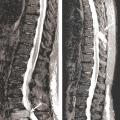

Les clichés standard du squelette axial (crâne, rachis, côtes et bassin) restent encore la référence pour diag­nostiquer une atteinte osseuse mais devraient être remplacés, en raison de leur faible sensibilité, par l’imagerie moderne. Les anomalies évocatrices sont une lyse à l’emporte-pièce (géode ou lacune), visible sur les os plats, associée ou non à une déminéralisation diffuse, ou sur les os longs avec résorption corticale et menace de fracture pathologique (fig. 4). Les lacunes peuvent être totalement asymptomatiques, notamment lorsqu’elles siègent sur le crâne. Les tassements vertébraux, plus ou moins complets, voire en galette, sont toujours symptomatiques. Le scanner du corps entier faible dose devrait remplacer les clichés standard en raison de sa plus grande sensibilité, de sa durée de réalisation plus courte et de sa plus faible dose délivrée d’irradiation. L’IRM du corps entier et le TEP-scan détectent 20 % de lésions supplémentaires par rapport aux clichés osseux standard sous la forme d’images nodulaires en hyposignal T1 et hypersignal T2 et STIR, pour l’IRM (fig. 5), ou de foyers hypermétaboliques correspondant aux lacunes sur le scanner, pour le TEP-scan (fig. 6). Ces examens sont particulièrement utiles dans les formes peu avancées de la maladie (absence d’anomalie sur les clichés standard), pour dépister une épidurite ou confirmer le caractère tumoral du tassement vertébral (IRM) et pour suivre l’évolution sous traitement (réponse métabolique au TEP-scan avec disparition des foyers hypermétaboliques). Leur utilisation est en cours de validation et limitée par leur accessibilité.